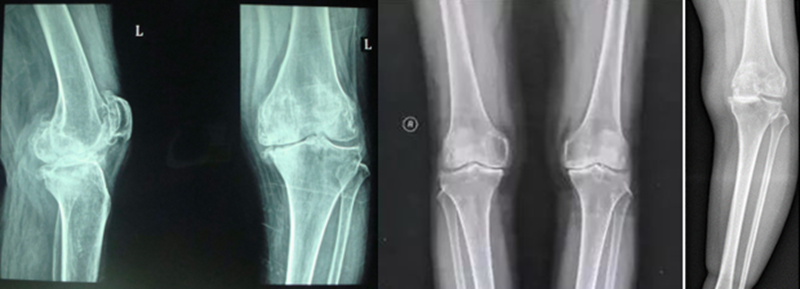

膝关节骨关节炎X片分级

0级:正常;

I级:关节间隙可疑变窄,可能有骨赘;

II级:有明显的骨赘,关节间隙轻度变窄;

III级:中等量骨赘,关节间隙变窄较明确,软骨下骨骨质轻度硬化改变,范围较小;

IV级:大量骨赘形成,可波及软骨面,关节间隙明显变窄,硬化改变极为明显,关节肥大及明显畸形。

(1)全膝关节置换术(Total Knee Arthroplasty,TKA):置换整个关节面,矫正力线,假体使用寿命较长,缓解疼痛疗效肯定。适用于整个膝关节软骨磨损严重,并伴有内翻畸形患者。

(2)单髁置换术(Uincomparmental Knee Arthroplasty,UKA):置换内侧部分关节面,可矫正轻度内翻,保留了患者所有的韧带,缓解关节内侧疼痛疗效确切,适用于内侧软骨磨损患者。